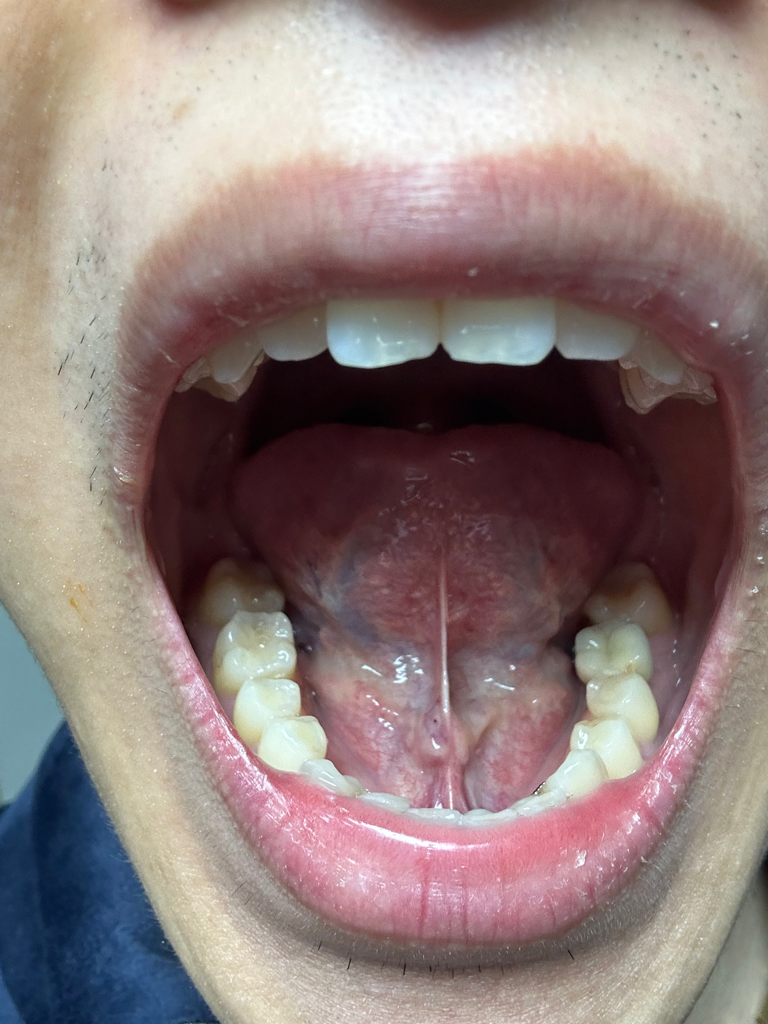

혹시 혀밑에 이거 침샘일까요?

모양이 왜이렇게 볼록한지 모르겠네요 저기가 침샘이라 그런걸까뇨? 모양이 이상하진 않나요?

혹시 이상 소견이 있을까요? 병원를 가야하는건지 정상인지 불편함은 없습니다.

• 2번 째 사진

혀밑샘의 침이 분비되는 구멍이 있어서 저렇게 볼록하게 생겼습니다. 정상적인 모습입니다.